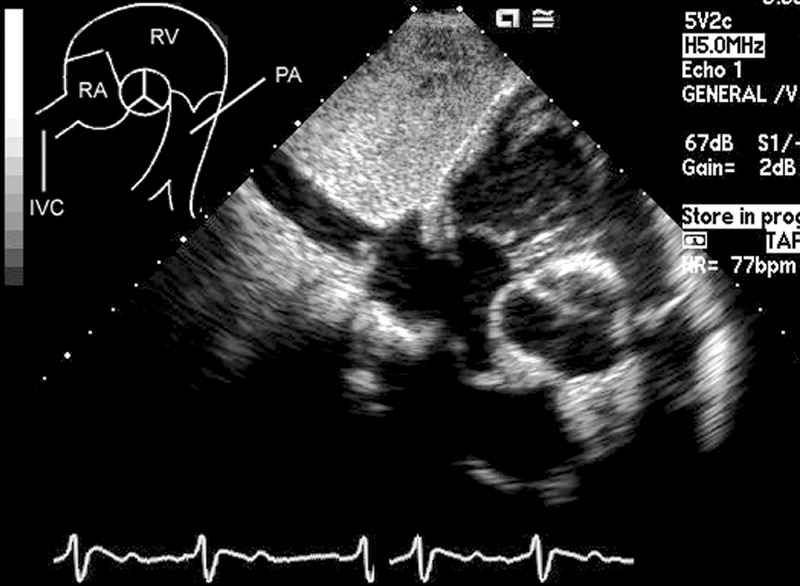

فحوصات تشخيصية لبعض امراض القلب والشرايين التاجية